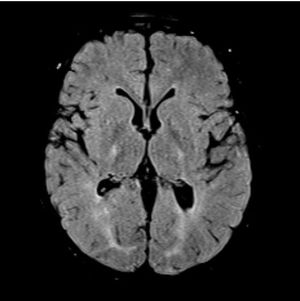

18q syndrome is a rare chromosomal anomaly where there is a deletion of part of the long arm of chromosome 18. Associated symptoms and findings vary widely, as does their severity. Characteristic features include short stature, mental retardation and hypotonia, facial and distal skeletal abnormalities.  Chromosome 18q syndrome appears to result from a spontaneous, sporadic chromosomal error during very early embryonic development.